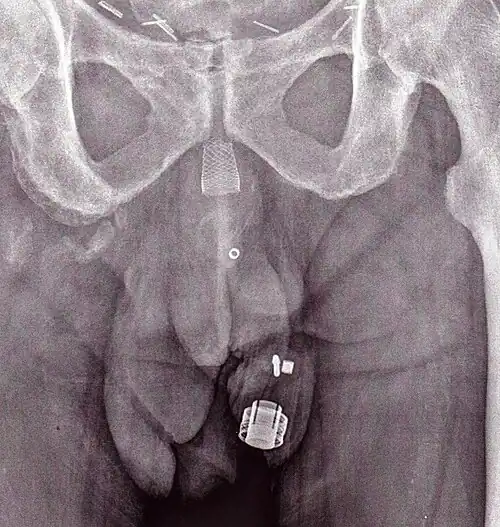

CT-Scan (koronale Rekonstruktion) zeigt ein AMS 800 bei einer Frau -

Ein Röntgenbild des implantierten ZSI 375. Das Gerät ist deaktiviert – die Feder wird unter der Oberseite des Zylinders zusammengedrückt. Der Patient ist inkontinent. -

Ein Röntgenbild des implantierten ZSI 375. Das Gerät wird aktiviert – die Feder wird oben am Zylinder dekomprimiert. Der Patient ist kontinent. -